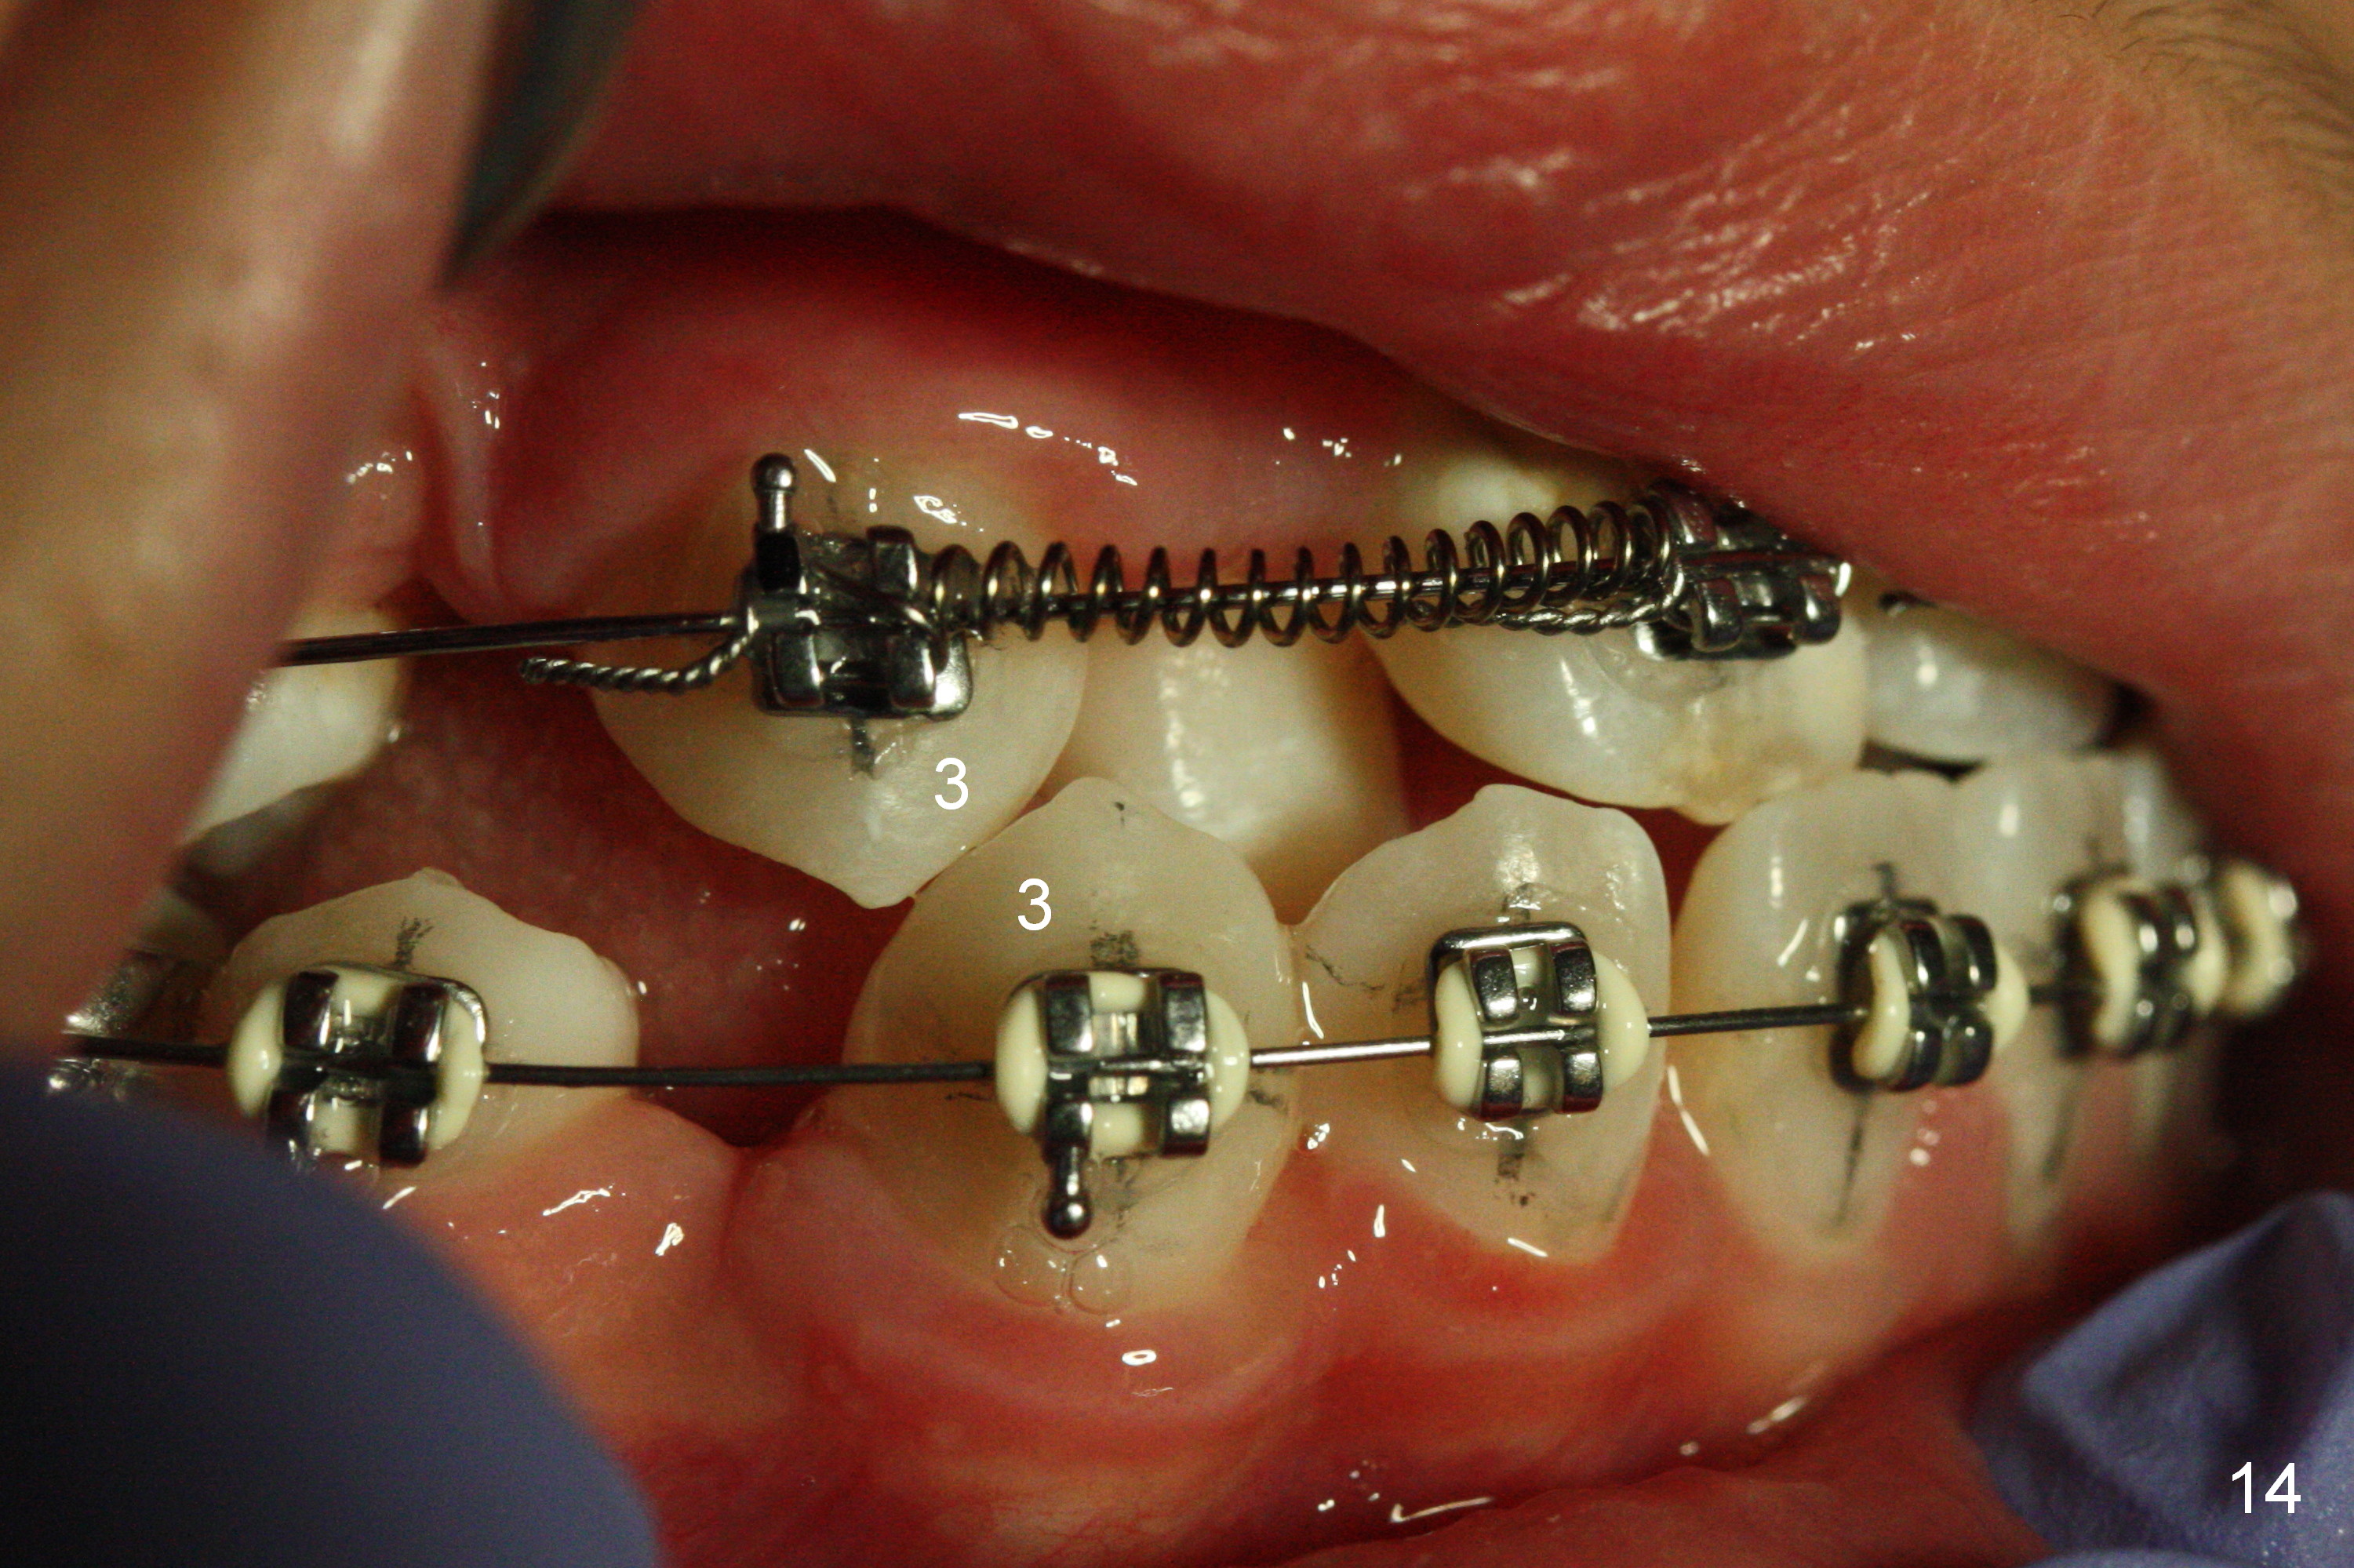

Another 1 month, the right canines (Fig.14: 3, as compared to the left side (Fig.15)) occlude each other, while LR2 has full engagement into .016 niti wire (compare to Fig.12,13). Open coil springs are placed with upper .018' ss arch wire. It must be easier to gain space for UR 2 (Fig.16) than UL2 (Fig.17), because of the presence of space on the right side (4 in Fig.16). There appears no space between UL 4 and 6.